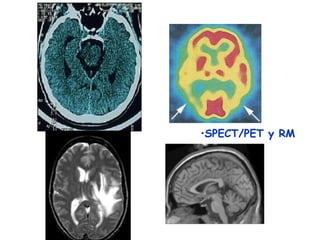

TAC: Con Rx, distingue lo que no se ve a los Rx

convencionales: tálamo, ganglios básales, sustancia gris y

blanca de la corteza, los ventrículos.“Estática no funcional:”

Resonancia magnética: crea una imagen del agua de los tejidos,

revela las principales regiones del SNC (hemisferios, cuerpo

•SPECT/PET y RM